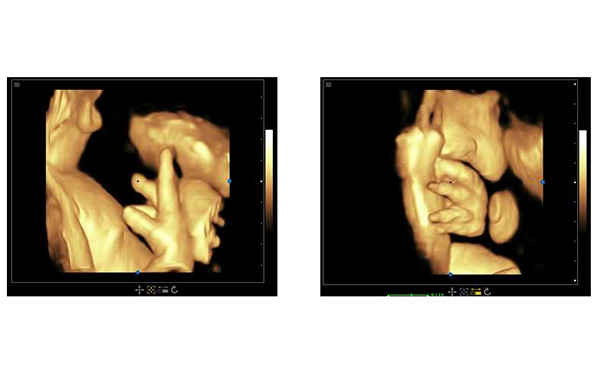

孕期B超檢查三個(gè)階段,大為醫(yī)療高端彩超孕期胎兒顯示

醫(yī)院用高端三維多普勒、4D成像技術(shù)的彩超可以參考大為醫(yī)療的高端彩超。